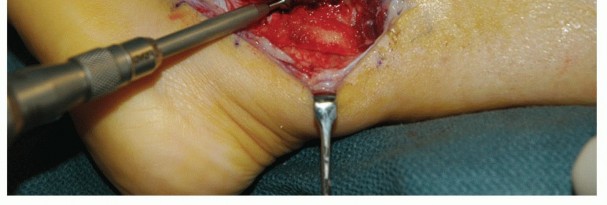

| From the distal fibular tip, introduce progressively larger diameter drill bits to weaken the distal fibula and ream away the distal fibular cancellous bone (TECH FIG 8). | |||

| Protect the dislocated tendons and adjacent soft tissues from the drill bit. | |||

| Although simple impaction of the posterior fibula to deepen the groove is possible at this point, we prefer to first weaken the cortex with a microsagittal saw as described for the traditional fibular groove-deepening | |||

| procedure (TECH FIG 9A). | |||

| To protect the smooth surface on the posterior fibula, a tamp can be placed longitudinally in the groove and impacted so as to avoid disruption of the smooth gliding surface for the peroneal tendons (TECH FIG 9B). | |||

| The peroneal tendons should remain reduced without manually restraining them (TECH FIG 10A). If not, then deepen the groove further with a larger diameter drill bit and perform further impaction of the posterior fibular surface. | |||

| Reattach the SPR to the posterolateral fibular margin via drill holes. | |||

| Be sure the peroneal tendons glide well without restriction in the deeper fibular groove (TECH FIG 10B). Standard closure | |||